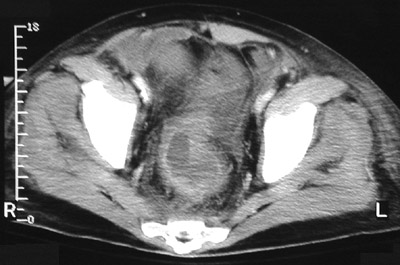

| The sigmoid colon seen in this pelvic CT scan reveals a thickened bowel wall. There has been prior bowel resection and this remaining segment continues to demonstrate changes associated with pseudomembranous colitis. This patient's stool was positive for Clostridium difficile toxin. He had received high-dose, broad spectrum antibiotic therapy for several weeks. |